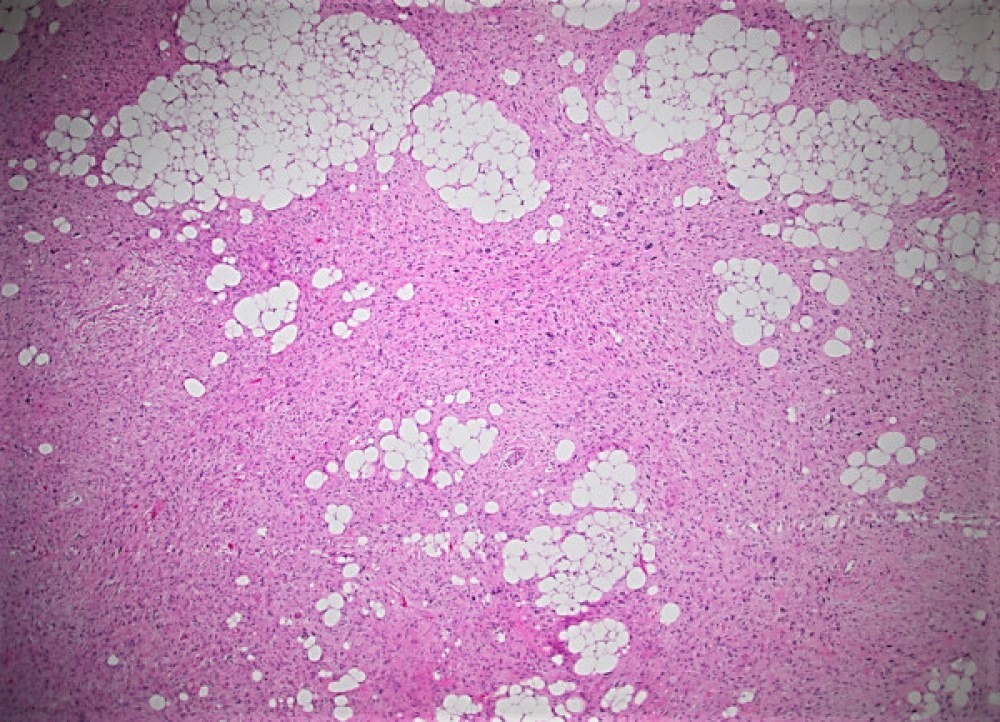

Sections of the biopsy revealed lobules of adipocytes admixed with the areas of an atypical spindle cell proliferation with moderately to markedly pleomorphic cells arranged in loose fascicles or storiform pattern within a fibrotic, focally myxoid stroma. Approximately 60-70% of the tumor was replaced by necrosis. Ki-67 proliferation index was 5-10%. Immunohistochemical staining demonstrated strong positivity with MDM2, CDK4 and p16 which supported the diagnosis.